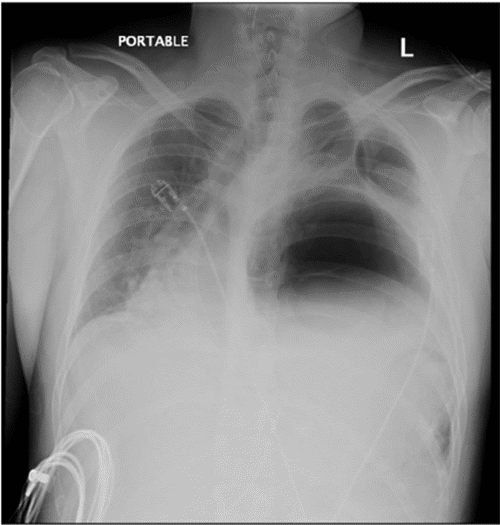

Our patient is a 30-year-old male with a remote history of a severe motor vehicle collision nine years prior, who presented to an outside hospital with several days of worsening abdominal pain and vomiting. A chest X-ray raised concern for a diaphragmatic hernia, leading to placement of a nasogastric tube at the outside hospital. Follow-up X-ray after placement with nasogastric suctioning showed no improvement (Figure 1). His condition continued to decompensate while awaiting transfer to our high-volume teaching hospital, ultimately requiring intubation and vasopressor support for hemodynamic instability.

Figure 1. Persistent Rightward Mediastinal Shift in Tension Gastrothorax. Published with Permission

Chest radiograph following nasogastric tube placement demonstrating persistent rightward mediastinal shift secondary to a large gastrothorax